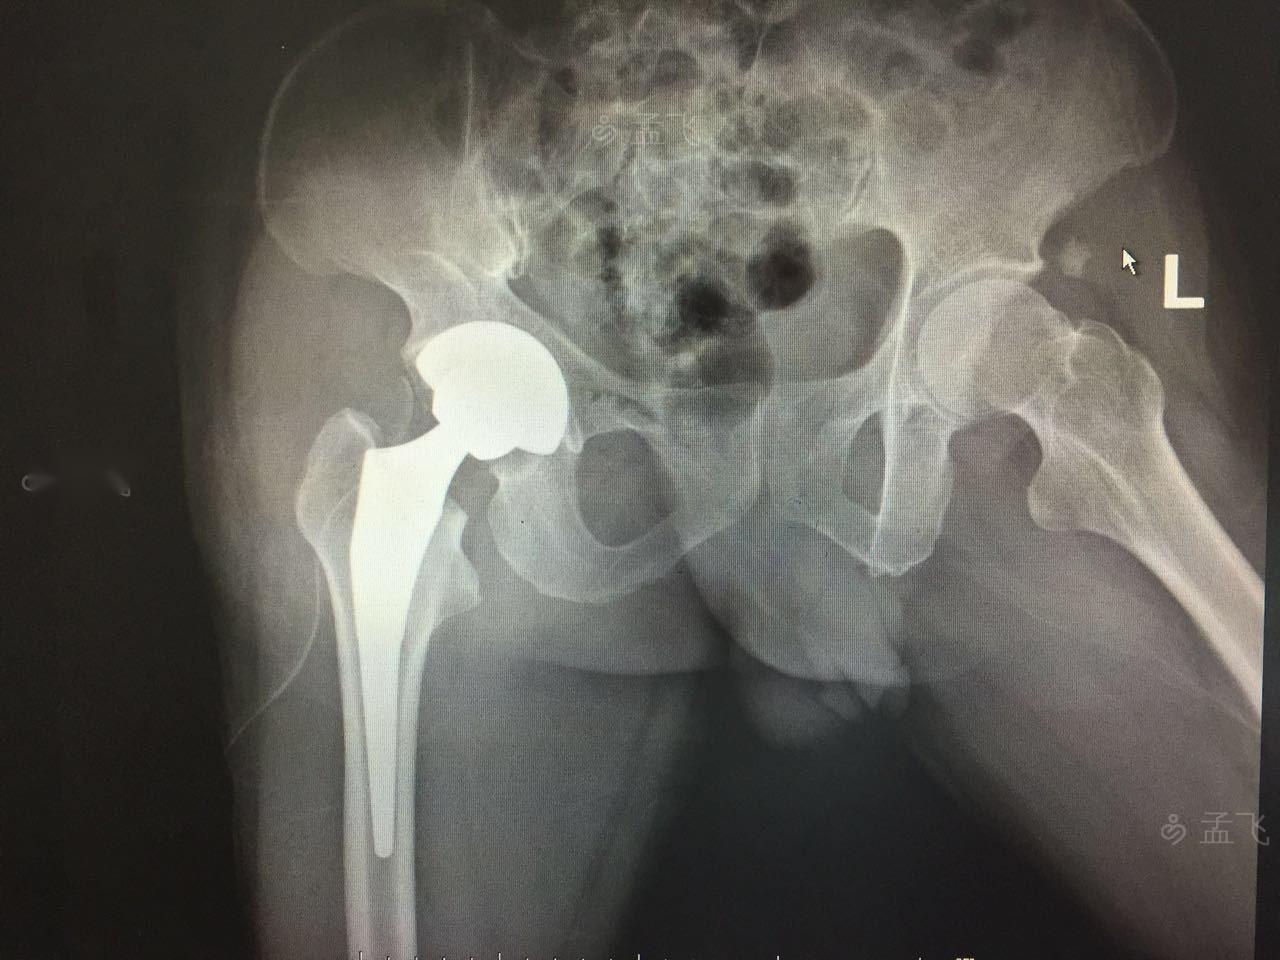

右人工全髋关节置换术后